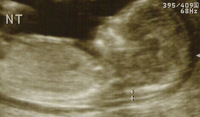

EmbarazoDurante el embarazo y las sucesivas ecografías que nos hacemos, uno de los recuerdos que permanecen en nuestra memoria son las medidas del feto, el peso y algún dato más. No obstante, la longitud del futuro bebé es uno de los datos de más...